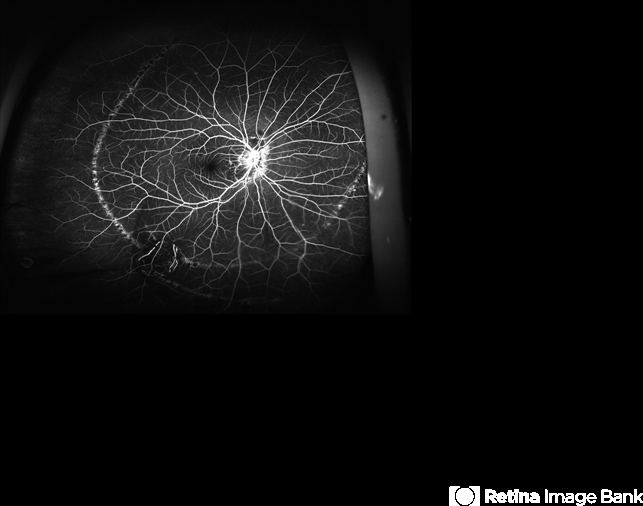

- PHOS, line

California ICG OPTOS - Description

- Hyperfluorescent, concentric, chorioretinal striae on fluoroangiography.